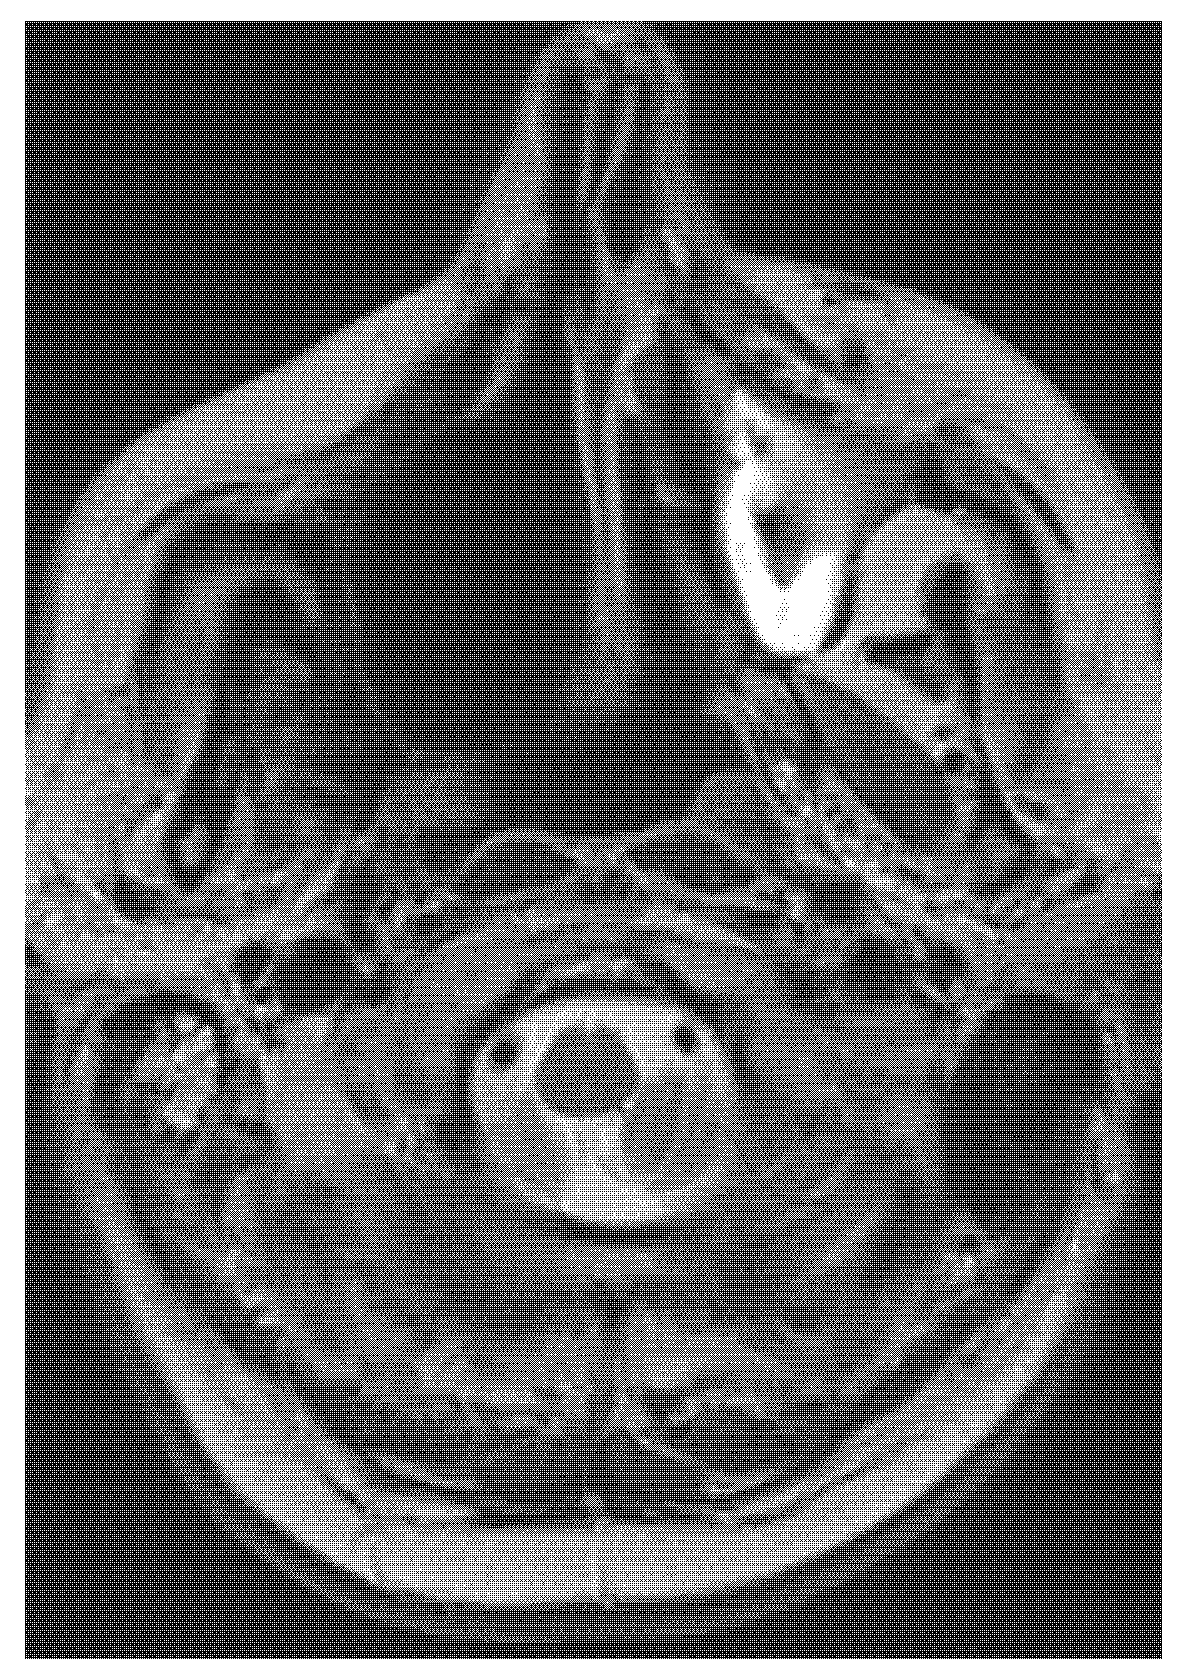

Highly Aggressive Osteosarcoma of the Ethmoids and Maxillary Sinus-A Case of Successful Surgery and Proton Beam Radiotherapy in a 65-Year-Old Man

2. Case Report (Observation)